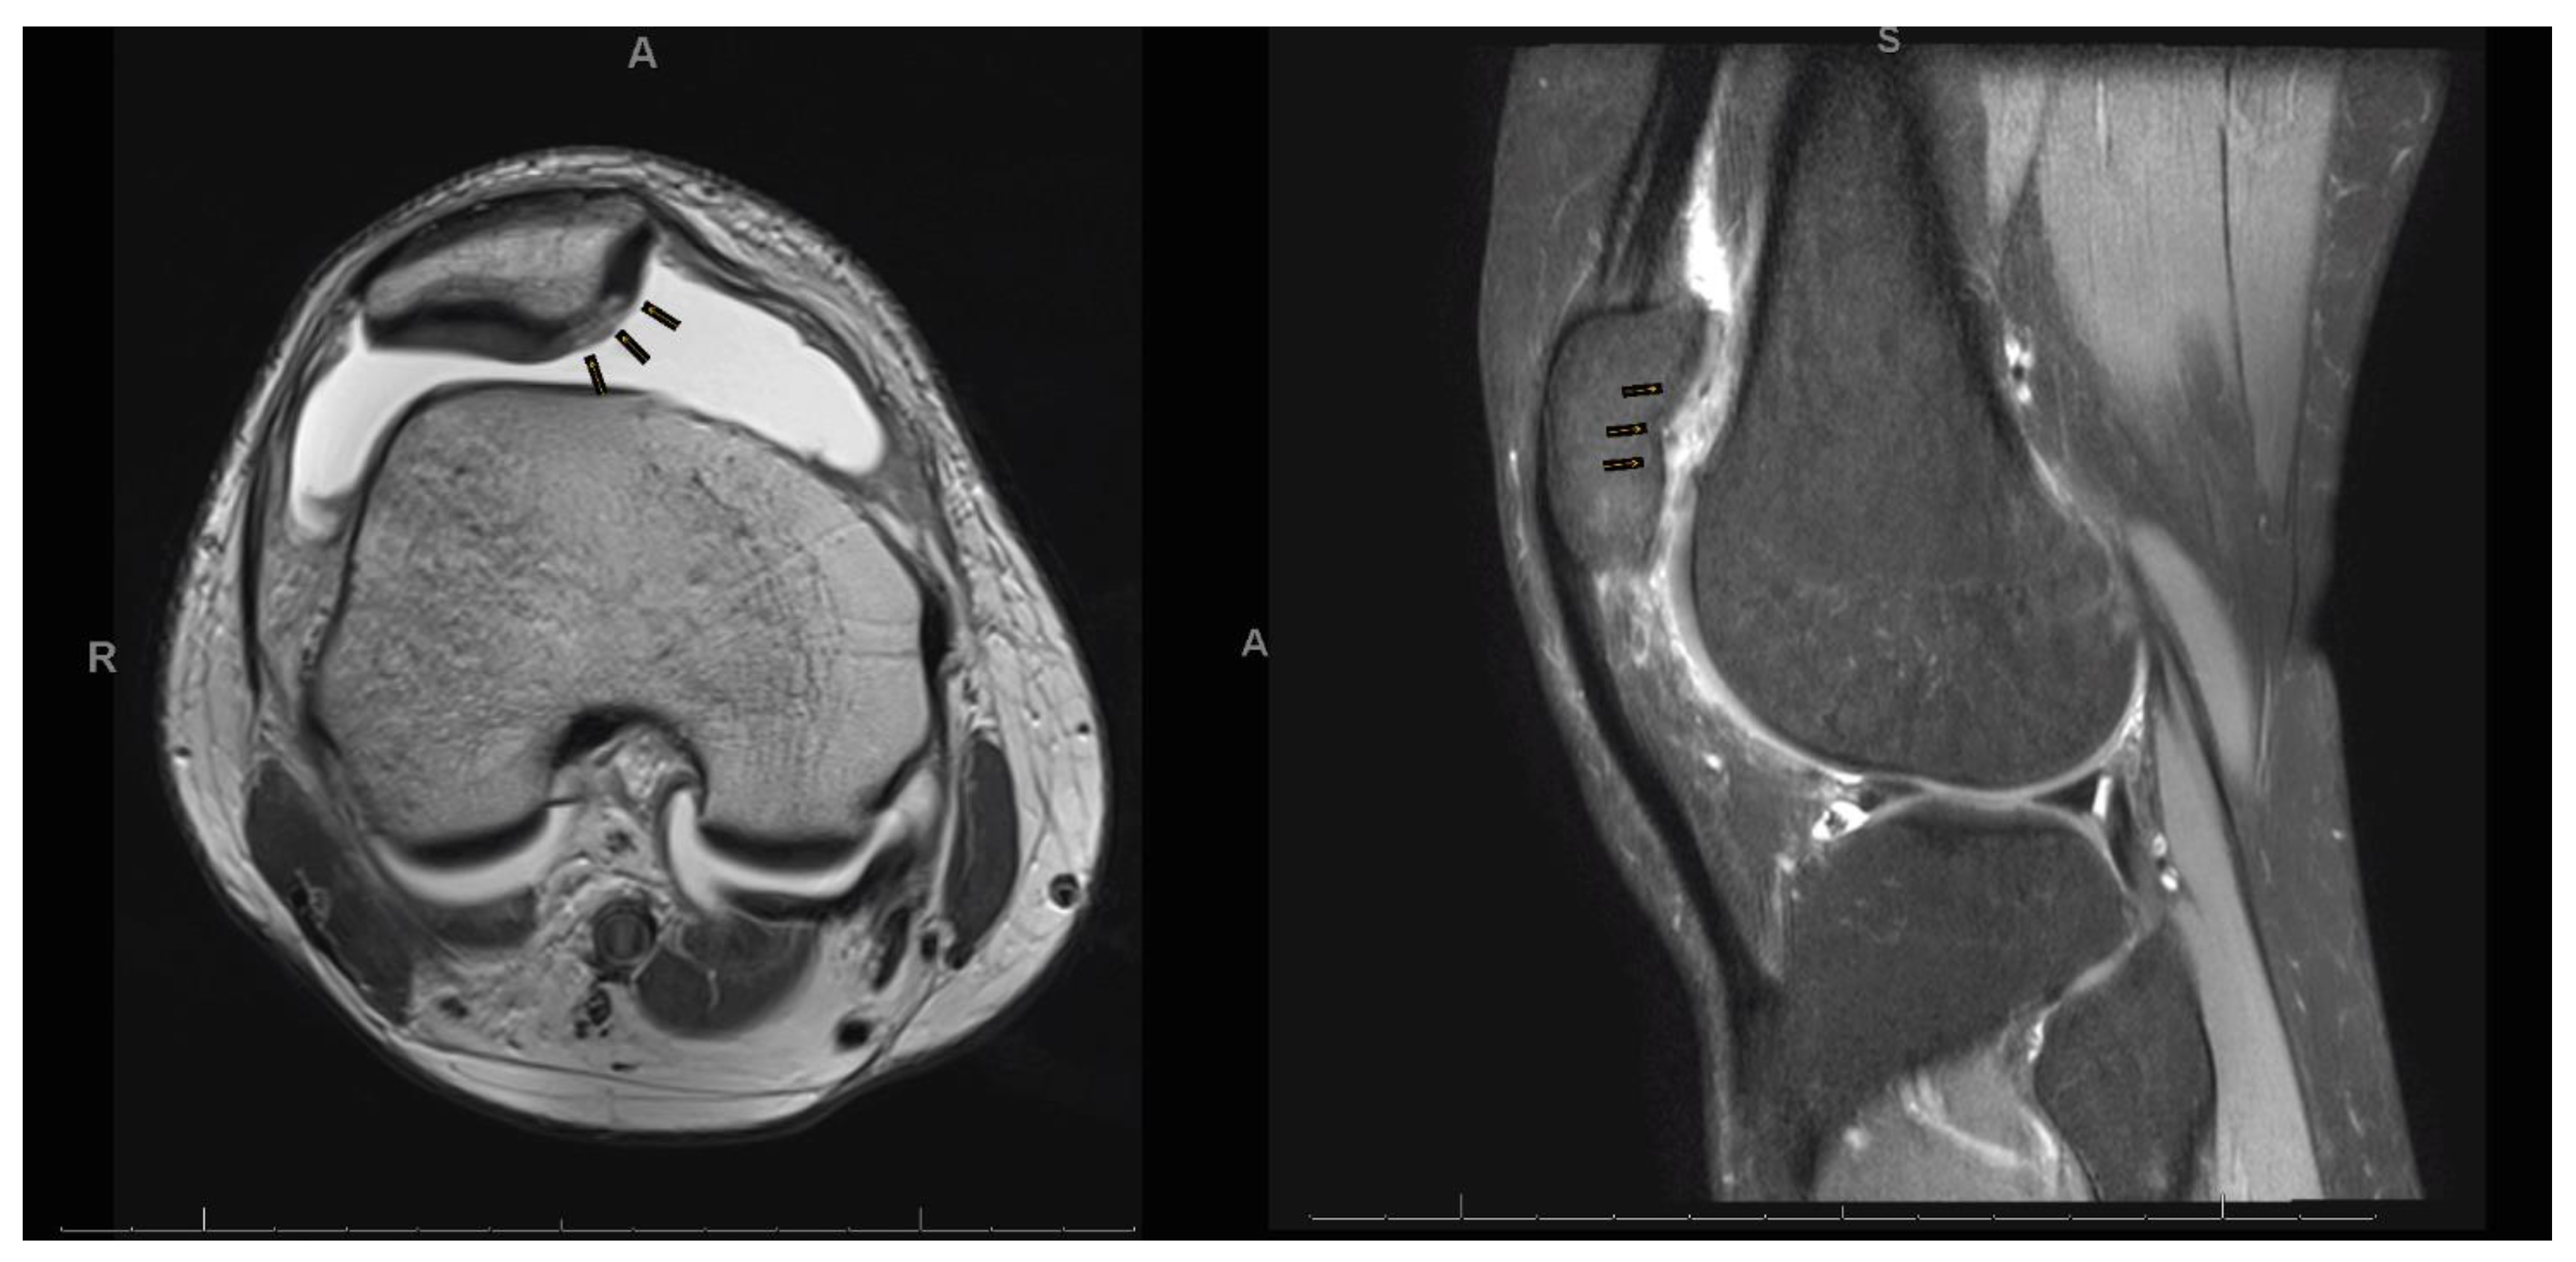

- Marlovits, S.; Singer, P.; Zeller, P.; Mandl, I.; Haller, J.; Trattnig, S. Magnetic resonance observation of cartilage repair tissue (MOCART) for the evaluation of autologous chondrocyte transplantation: Determination of interobserver variability and correlation to clinical outcome after 2 years. Eur. J. Radiol. 2006, 57, 16–23. [Google Scholar] [CrossRef]